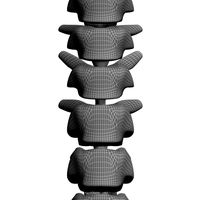

Human spine T10-L5 - male

This model represents a human backbone T10-L5

The 3D rendering was created using medical scan data - CT scans. Patient's description: age 32, male PLEASE NOTE THAT part of ribs, sacrum, and T10 vertebra in the 3D model are cut off due to lack of 2D medical scans (all parts that have been included are shown in the photos) the objects in the model are non-manifold The 3D model was created in order to familiarize students, doctors and curious folk with anatomy of human spine vertebra skeleton spine vertebrae human lumbar backbone thoracic real skeletal ribs ct bone bones science medical thorax anatomical anatomy torso human anatomy medical anatomy real human

The 3D rendering was created using medical scan data - CT scans. Patient's description: age 32, male PLEASE NOTE THAT part of ribs, sacrum, and T10 vertebra in the 3D model are cut off due to lack of 2D medical scans (all parts that have been included are shown in the photos) the objects in the model are non-manifold The 3D model was created in order to familiarize students, doctors and curious folk with anatomy of human spine vertebra skeleton spine vertebrae human lumbar backbone thoracic real skeletal ribs ct bone bones science medical thorax anatomical anatomy torso human anatomy medical anatomy real human